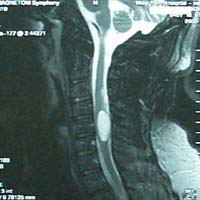

<¸ñµð½ºÅ©>

<¼ö¼úÀü>

<¼ö¼úÈÄ>

¾çÃø

»óÁö ÅëÁõÀ» ÁÖ¼Ò·Î ³»¿øÇÑ È¯ÀÚÀÇ °æÃߺÎ

MRI¼Ò°ß, ¼ö¼úÈÄ ¼Ò°ß